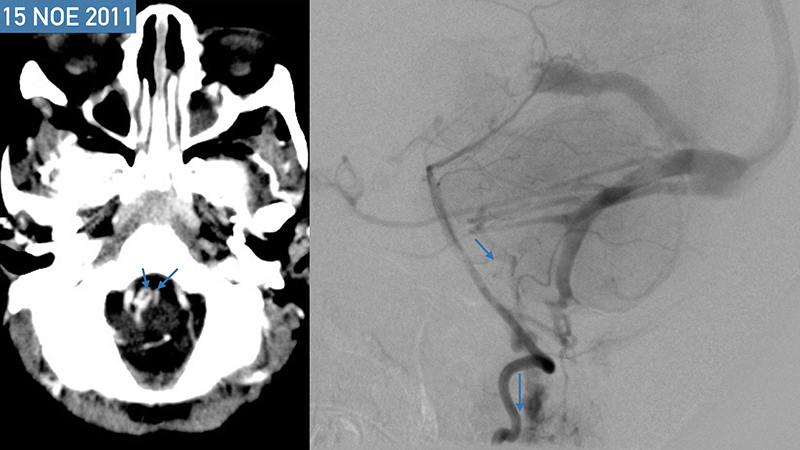

- Στην αξονική τομογραφία πρό μηνός, βλέπουμε υποφλοιώδεις και υποεπενδυματικές μικροαποτιτανώσεις αποτέλεσμα μικροϊσχαιμικών αλλοιώσεων εξαιτίας της φλεβικής υπερτάσεως. Συνυπάρχει αρχόμενη διάταση των κοιλιών.

- Στην αξονική τομογραφία εισαγωγής του, μετά σκιαγραφικό βλέπουμε επέκταση των μικροϊσχαιμικών αλλοιώσεων στο εγκεφαλικό στέλεχος με πρόσληψη σκιαγραφικού,

Το παιδί μετά τον πρώτο εμβολισμό παρουσίασε άμεση κλινική βελτίωση, με πλήρη αποκατάσταση της κινητικότητος του. - Προσθιοπίσθια λήψη κατά την έγχυση στην αριστερή έσω καρωτίδα ένα μήνα μετά την επέμβαση. Παρατηρείται θρόμβωση του ευθέως κόλπου και της περιοχής του Ληνού του Ηροφίλου καθώς και του τελικού τμήματος του άνω οβελιαίου κόλπου και των εγκαρσίων κόλπων. Ο μηχανισμός της θρομβώσεως, αποδίδεται στην σημαντική ελάττωση της ροής μέσα στο φλεβικό αποχετευτικό δίκτυο της φλέβας του Γαληνού και του ευθέως κόλπου που πιθανότατα οδήγησε σε φλεβική στάση και θρόμβωση.

- Πλαγία λήψη κατά την έγχυση στην αριστερή έσω καρωτίδα ένα μήνα μετά την επέμβαση. Παρατηρείται ελάχιστη άρδευση της επικοινωνίας από οπίσθιους χοριοειδείς κλάδους των οπισθίων εγκεφαλικών, καθώς και από θαλαμοδιατιτραίνοντες κλάδους που εκφύεται από το Ρ1 της αριστερής οπισθίας εγκεφαλικής αρτηρίας. Η φλεβική παροχέτευση της επικοινωνίας γίνεται προς την φλέβα του Γαληνού που είναι σημαντικά λιγότερο διατεταμένη, και δια μέσου επιπολής φλεβός της έσω επιφανείας του αριστερού βρεγματικού φλοιού προς τον αποσυμφορημένο πιά άνω οβελιαίο κόλπο. Η φλεβική αποχέτευση του ημισφαιρίου γίνεται προς το σύστημα του αριστερού σηραγγώδους κόλπου, με σημαντική αιμοδυναμική αποσυμφόρηση των ημισφαιρικών φλεβών που πλέον σκιαγραφούνται σε φυσιολογικό χρόνο.

- Προσθιοπίσθια λήψη κατά την έγχυση στην αριστερή σπονδυλική αρτηρία. Επανελέγχεται ελάχιστη υπολειμματική άρδευση της επικοινωνίας από οπίσθιους χοριοειδείς κλάδους των οπισθίων εγκεφαλικών, καθώς και από θαλαμοδιατιτραίνοντες κλάδους που εκφύεται από το Ρ1 της αριστερής οπισθίας εγκεφαλικής αρτηρίας, με θρόμβωση του ευθέως κόλπου και της περιοχής του Ληνού του Ηροφίλου καθώς και του τελικού τμήματος του άνω οβελιαίου κόλπου και των εγκαρσίων κόλπων.

- Πλαγία λήψη κατά την έγχυση στην αριστερή σπονδυλική αρτηρία. Η φλεβική παροχέτευση γίνεται προς την φλέβα του Γαληνού, και διά μέσου επιπολής φλεβός προς την έσω επιφάνεια του αριστερού βρεγματικού λοβού προς τον άνω οβελιαίο κόλπο, κατά την μετάπτωση του μέσου προς οπίσθιο τριτημόριο. Επίσης μέσω υποεπενδυματικών φλεβών που πορεύονται ενδοκοιλιακά αμφοτερόπλευρα και εκβάλλουν διά των άνω λιθοειδικών φλεβών προς το τους εγκαρσίους κόλπους, με πορεία προς τοην περιοχή του Ληνού που φαίνεται να έχει επανασηραγγοποιηθεί. Παρατηρείται αποσυμφόρηση του περιμεσεγκεφαλικού φλεβικού δικτύου με σημαντική ελάττωση της φλεβικής συμφορήσεως περιμεσεγκεφαλικά καθώς και προς τον νωτιαίο μυελό.